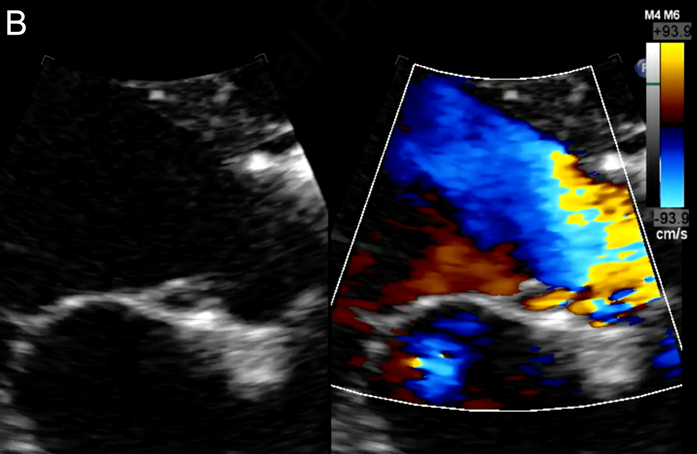

- 2차원 경흉부 심장초음파 검사에서 대동맥 판막 소엽에 부착된 낭종 형태의 구조물이 확인되었습니다. 이 낭종은 직경 8mm의 둥근 무에코 병변으로, 얇은 고에코성 벽을 가지고 있었으며, 좌측 관상동맥 첨판 바로 아래 대동맥 판막 소엽과 밀접하게 접촉해 있었습니다.

- 도플러 검사 결과, 낭종 내부에 액체가 채워져 있으며 대동맥 및 심실 내강과 연결되어 있음이 확인되었습니다. 특히 이완기 동안 낭종 내에서 난류가 관찰되었고, 이는 좌심실 유출로와 연속성을 보여 대동맥 판막 부전의 형성에 기여하는 것으로 나타났습니다.

- 중등도 대동맥 판막 부전이 동반되었으며, 좌심방은 경미하게 확장되어 있었습니다. 대동맥 판막의 첨판은 3개였고 두꺼워지지 않았으며, 대동맥 궁은 확장되지 않았습니다.